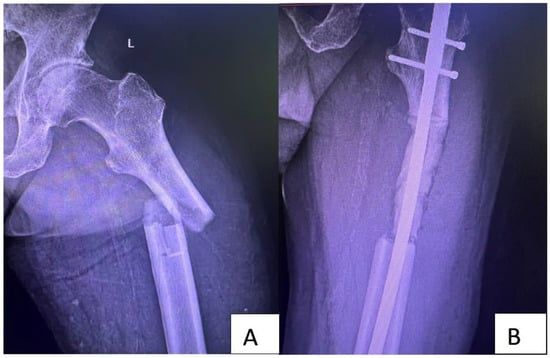

5.3. Treatment of Complete or Impending Fractures in Unique Bone Metastasis following Lung Cancer—Resection Followed by Intramedullary Nails and Acrylic Bone Cement